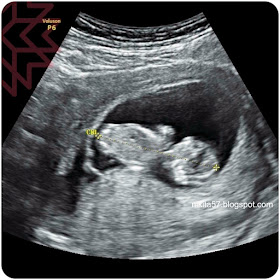

照了超音波看,有明顯寶寶的樣子了,

當超音波測到心跳的時候,心情很複雜很想哭,

知道寶寶還是心跳蹦蹦蹦的,真的很開心,雖然那時候只有11週的相處,

而超音波照的結果,不尋常的是左下方有黑色的陰影,

醫生說,就是那邊在出血!!!!!

而且,不是息肉出血(表示事情更嚴重!)

醫生說,因為超音波左下黑色的部分,其實就是血,

要讓它消失,就是只能慢慢的讓它流光,自己痊癒,